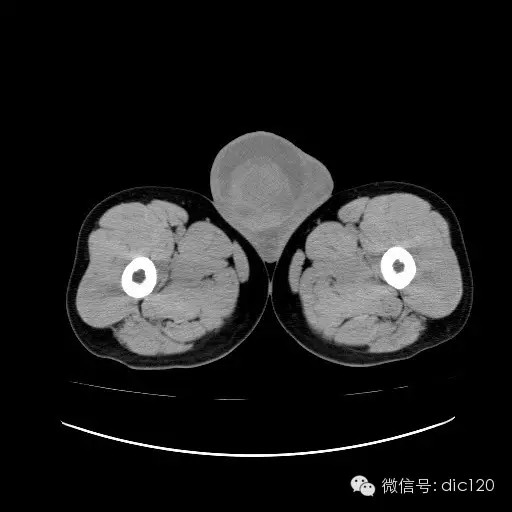

【影像表现】

青年男性,右侧睾丸肿大,边界清晰,增强后睾丸不均匀中度强化,内可见多灶囊变坏死区,动脉期肿块内有细小动脉血管显示,延迟期可见分隔样强化,鞘膜囊可见积液。

定位定性:右侧睾丸恶性肿瘤。

【影像诊断】

右侧睾丸精原细胞瘤,右侧睾丸鞘膜积液。